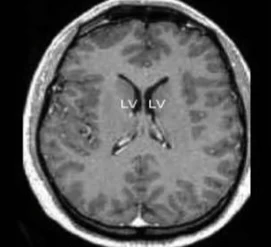

در نمونه ای نادر، یک فرد با از دست دادن حدود ۹۰ درصد از مغز خود همچنان از هوشیاری کامل برخودار است. این اتفاق باعث شده که دانشمندان بار دیگر بر نظریههای خود و تعریف هوشیاری از نظر بیولوژیکی بازنگری کنند. با زومیت همراه باشید تا در مورد این نمونهی پزشکی بیشتر بحث کنیم.